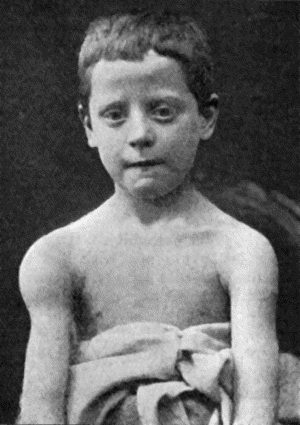

| 43. | Facies of Inherited Syphilis | 174 |

| 44. | Facies of Inherited Syphilis | 175 |